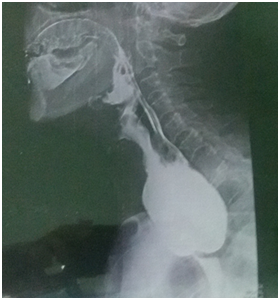

All six patients were symptomatic Four of patients were male. Age of patients was 65 to 80years. Four of patients came with dysphasia aspiration, halitosis, and malnutrition and regurgitation, one of this patient present three period with aspiration pneumonia and hospital admission. One of patients underwent endoscopic diverticulotomy and 24 hour after this procedure present with odynophagia, fever and neck subcutaneous emphysema With B-swallow perforation of diverticula was demonstrated, this patient underwent neck exploration and diverticulectomy and drainage. Diagnostic tools of five cases was B-swallow and esophagoscopy (Figures 1-5). One came with food marital retention and pain and neck mass tender mass. One patients referred with erithem, redness and criptation of neck with diagnosis of diverticulitis (Figures 6 & 7). Two cases underwent flexible endoscopic diverticulotomy, one failed and another ones complicated with perforation. The most common surgical approaches was diverticulectomy and myotomy in four patients (Figures 8 & 9). Food debris was present in one patient (Figure 10). Two of patients underwent diverticulectomy without myotomy. Complication and mortalities were zero. In two years flow-up, Outcome was good.

Figure 1 Show swallow of a 75 year old man with huge Zenker's diverticulum.